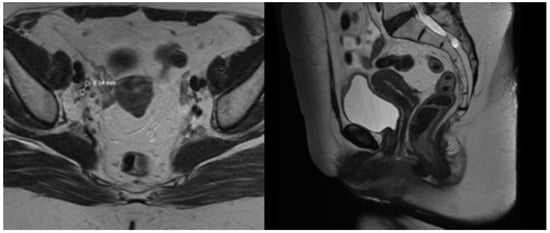

After pre-treatment quality assurance, the patient began the external beam IGRT and concurrent chemotherapy with Cisplatin 40 mg/kg weekly. The first Cisplatin infusion was given with the first fraction, and the patient received a total number of five cycles. External beam radiotherapy (EBRT) was performed on a linear accelerator Elekta Synergy Platform with daily cone beam CT imaging ensuring the proper patient set-up and reproducible bladder and rectum filling. The EBRT was delivered in 38 days. The treatment was well tolerated by the patient, and no early toxicity was detected during the chemoradiation course. She was scheduled for an MRT scan two days before the last EBRT fraction to assess the tumor response, depth of uterine cavity, and preferred angle of the tandem for cervical brachytherapy. The MRT scan revealed that the gross tumor had shrunk to 15 mm in its maximal diameter, and all previously enlarged lymph nodes were undetectable except for the right external iliac lymph node, the size of which decreased from 29 mm to 15 mm with a necrotic center (Figure 4). After gynecological examination and signing an informed consent, the patient was scheduled for intracavitary electronic brachytherapy (EBT).

Figure 4.

T2 weighted MRT images after EBRT.